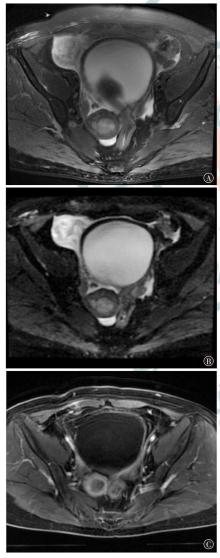

Ishikawa M, Nakayama K, Ishibashi T, et al. Case series of cerebral infarction with trousseau's syndrome associated with malignant gynecological tumors[J]. Mol Clin Oncol, 2016, 5(1): 138-142. DOI: 10.3892/mco.2016.888.